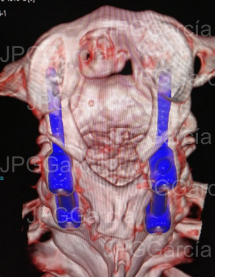

ESTUDIO DE CONTROL TOMOGRÁFICO CON COLOCACIÓN DE TORNILLOS Y BARRAS AL ATLAS Y AXIS